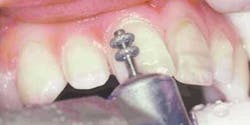

Preparation of the four incisors was then initiated using diamond burs from the Shofu Contemporary Cutting Kit (Figure 5). With the high-speed ElectroTorque KaVo handpiece, a small round diamond (0872-1) was used to outline the peripheral margins of the preparations (Figure 6). By scoring the facial surface of the incisors with the depth cutter (0897-1) (Figure 7), smooth and uniform tooth structure removal using a coarse tapered diamond (0835C-1) was facilitated (Figure 8). As tooth nos. 9 and 10 were prepared, it came time to address the gingival contour issues of the inflamed interproximal gingiva.